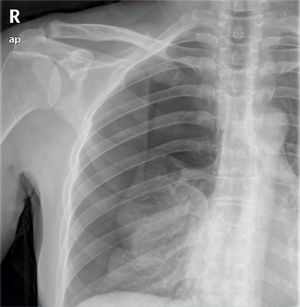

Se realiza radiografía de tórax donde se visualiza neumotórax derecho completo (fig. 1). En la analítica sanguínea no se objetivan alteraciones significativas.